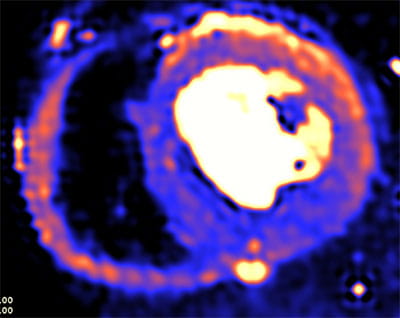

• Dedicated state-of-the art Cardiac MRI and CT imaging program (1.5T Siemens Aera; Dual-Source Siemens Force, Siemens Drive, and Flash scanners) with dedicated CMR techs and CT techs.

• High volume program with daily case averages of 10 CMR studies and 25-35 cardiac CTAs (50% coronary CTA, 30% structural, 20% other). Broad case complexity, including CAD, structural heart pathologies, congenital heart disease,  and implantable devices. Routine use of cutting edge technology, including T1/ECV mapping, quantitative perfusion, free-breathing CMR exam, artificial intelligence based CT analyses, CT-FFR, structural planning and simulation.